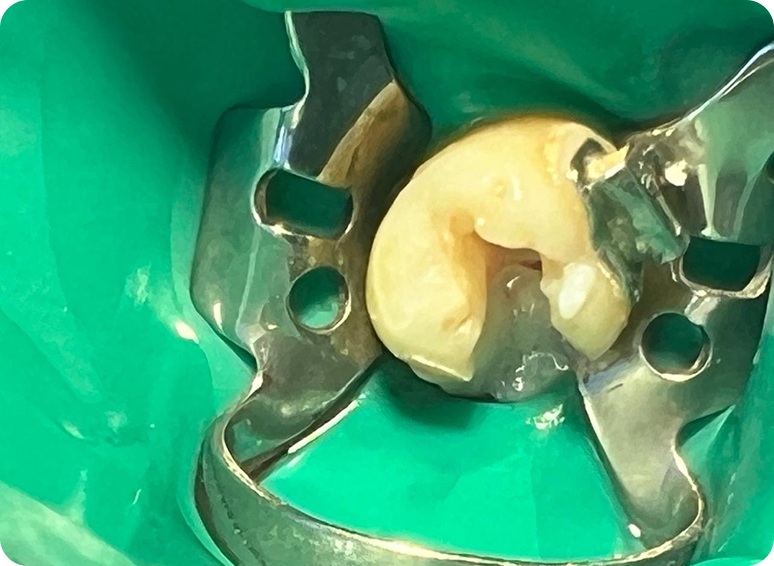

Removemos el tejido inflamado o infectado del interior del diente o muela, limpiando y desinfectando dentro las raíces.

El procedimiento se lleva a cabo con modernas técnicas y anestésicos de comprobada efectividad que reducen al mínimo cualquier molestia.